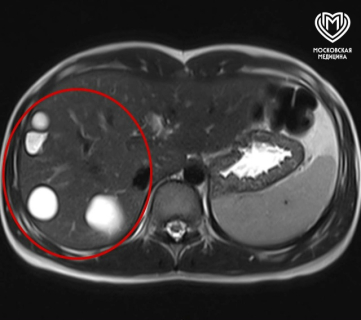

Пациентку госпитализировали в больницу после обследования, в ходе которого обнаружили случайную находку — крупные эхинококковые кисты в печени (их было пять штук).

Девочку подготовили к операции и удалили пять кист, используя современный высокотехнологический метод — иссечение под лапароскопическим контролем. Вначале с помощью пункции ввели препарат, который уничтожает личинок, после удалили содержимое новообразований, а затем извлекли их хитиновые оболочки.